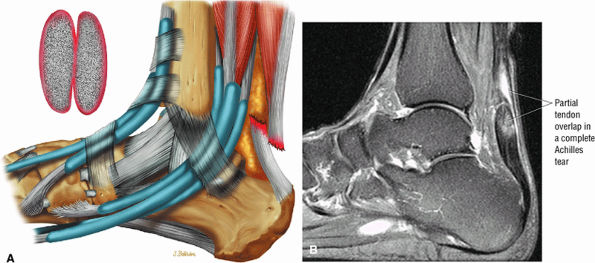

FIGURE 5.127 ● Partial overlap of torn Achilles tendon ends. (A) Lateral color illustration. (B) Sagittal FS PD FSE image.

A fluid-filled gap with or without interposed fat at the tear site in complete tendinous disruptions with discontinuity

Fraying or corkscrewing (see Fig. 5.123) of the tendon edges associated with proximal tendon retraction

In the absence of overlapping tendon edges, no tendon fibers can be seen at the tear site on axial images.

Tendon disruption with discontinuity and a wavy retracted tendon

Partial tears demonstrate hyperintense signal with incomplete anterior-to-posterior or posterior-to-anterior extension on FS PD FSE images.

Complete tears demonstrate a hyperintense fluid-filled tendinous gap.

Tendon rupture usually occurs 2 to 6 cm superior to the os calcis.

The size of the rupture varies, based on the degree of tendon retraction.

Ruptures demonstrate diffuse convexity of the anterior margin and enlarged tendon ends at the tear site.